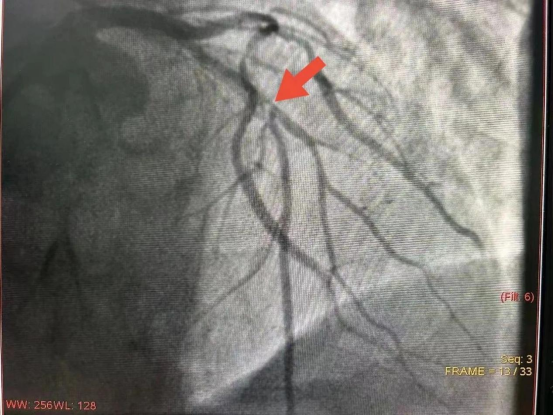

患者李先生,51岁,不稳定型心绞痛病史多年,冠状动脉造影提示冠脉三支病变伴有严重钙化,尤其前降支狭窄程度达到90%以上,并伴有360度环形重度钙化。严重钙化病变是介入治疗的难点之一,往往导致手术难度和风险呈几何倍数增加,钙化病变难以突破和扩张,极易发生血管夹层、穿孔和破裂等情况;在后续支架治疗中,若钙化病变未充分扩张,极易出现支架膨胀不良,贴壁不良,支架脱载进而导致急性、亚急性支架内血栓形成,支架内再狭窄等情况出现,均会直接危及患者生命。

△术前造影